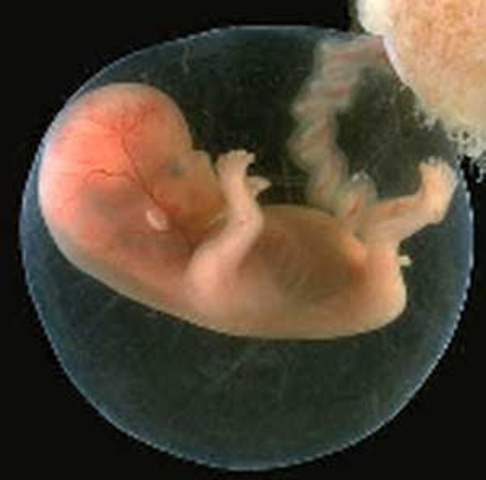

mide 3cm, la cara adquiere aspecto humano, se pueden ver los ojos, nariz, boca, los dedos estan bien formados

El feto mide 3 cm pesa enttre 15 y 20 gramos,

.Comiena a esbosearse kas uñas, ek refkejo de succion

Su longitud es de 16 cm y pesa 100 y 120 gramos -La cara tiene rasgos individuales. -Los movimientos pueden ser percibidos.-El bebe ya escucha ruidos , puede percibir Luz, reacciona mediante la lluz